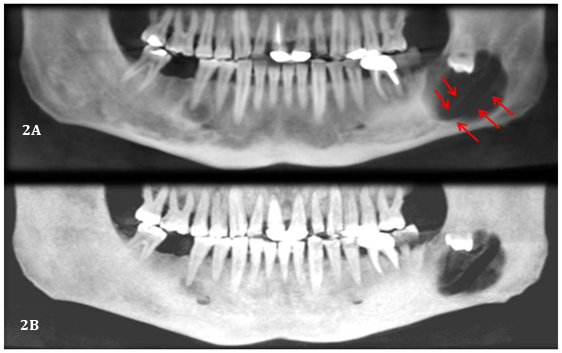

A CBCT was performed to identify the extension of the lesion and its relation with the IAC. Panoramic reconstruction (Figure 2A & 2B) shows a well-defined low density unilocular lesion circumscribing the crown of tooth #38 located vertically from the mid ramus extending below the level of the IAC, horizontally it extend from the apical third of the mesial root of #37 till the mid portion of the ascending ramus. Axial cuts (Figure 3) show expansion of the alveolar process and thinning and interruption of both lingual and buccal cortical plates. The roots of #37 show no resorption. The lesion is attached to tooth #38 at the level of the CEJ (Figure 4). The ectopic position of the IAC is also seen very clearly in the maximum intensity projection panoramic reconstruction (Figure 2B) and in the cross sectional images which shows the canal within the lesion (Figure 5A & 5B). After clinical and radiographic examination, a provisional diagnosis of dentigerous cyst was made; however, kerato cyst odontogenic tumor, amleloblastoma, ameloblastic fibroma were also considered in the differential diagnosis. Keratocyst don’t expand the bone to the same degree as presented here and attachment to the teeth will be more apically. Ameloblastic fibroma usually occurs in young patients which is not the case. Ameloblastoma would have presented internal septa if big in size as in this case. The most probable diagnosis is dentigerous cyst. The operation was performed under local anesthesia. Incision was made followed by raising a full thickness buccal mucoperiosteal flap. The lesion was then identified and the canal was viewed and confirmed, as seen on CBCT, to be passing in the center of the lesion. Dissection of the lesion away from the canal was performed using a tissue holder. With proper identification and isolation, the inferior nerve was preserved and the cyst was totally enucleated. Tooth number #38 was removed, and preservation of tooth #37. No sign of paresthesia was recorded after surgery. The surgical specimen was then sent for pathological analysis for final diagnosis. The histological examination showed a cystic lumen with blood content, a very thin lining of non-keratinized stratified squamous epithelium and dense fibro cellular connective tissue stroma with chronic inflammatory infiltrate. A macrophage and giant cell granuloma is noted around cholesterol crystals. There is no evidence of malignant change. The cyst opened measured 4x2x1 cm. A chronic inflamed dentigerous cyst was confirmed. Follow up CBCT was done after 3years of the surgery, and a progressive improvement in bone regeneration and healing process at the site of surgery was observed (Figure 6A & 6B); vitality test on tooth #37 response was positive.

Figure 2A Panoramic reconstruction showing the ectopic position of the IAC.

Figure 2B Maximum intensity projection confirming the IAC position.

In our case, a CBCT was made after primary investigation of the case by panoramic radiograph to show the exact extend of the lesion. Panoramic reconstruction showed a well-defined corticated unilocular homogeneous low density lesion associated with the crown of the unerupted inverted wisdom tooth #38, occupying the angle of the mandible. The lesion shows bucco-lingual expansion and interruption of cortical plates, no root resorption on the adjacent tooth (#37) and displacement of the affected tooth (#38) in coronal direction. In relation with the mandibular canal, there was no remarkable change in the position, which contradicts the benign aspect of the lesion and its slow growing rate. Slowly growing lesions will have adequate time for remodeling and subsequent pushing of the canal. This was not present in our case, whereas the lesion continued its slow growing process around the mandibular nerve, without any change in its position and without any clinical signs.